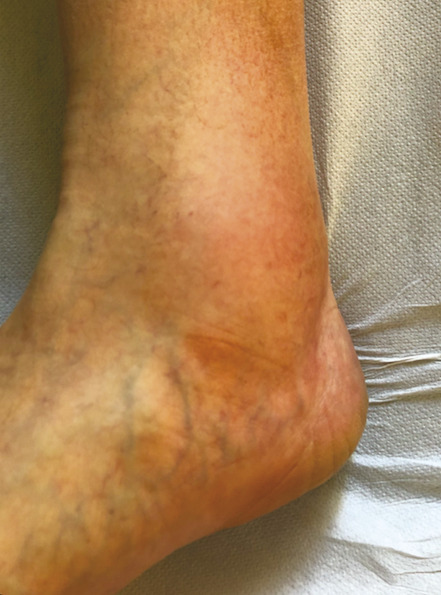

Ce retentissement tissulaire peut être plus important avec la survenue de troubles trophiques qui peuvent intéresser la peau et le tissu sous-cutané et sont classifiés C4 : dermite ocre qui apparaît au tiers inférieur de jambe (fig. 5 ), dermite de stase circonscrite en regard d’un trajet variqueux ou plus diffuse au niveau de la jambe et, dans les stades encore plus avancés, hypodermite scléreuse (C4b) siégeant au-dessus de la cheville au tiers distal et moyen de la jambe (fig. 6 et 7). Une atrophie blanche est aussi possible ; elle se traduit par une zone cicatricielle le plus souvent à la face médiale du tiers inférieur de la jambe.

La corona phlebectatica (C4c) constitue un signe de gravité de la maladie variqueuse qui expose au risque de décompensation tissulaire. Elle s’observe au niveau périmalléolaire interne sous la forme d’un amas en couronne de télangiectasies associées à une dilatation de capillaires et de veinules sous-cutanées réalisant des formations cupuliformes et des taches de stase (fig. 9).